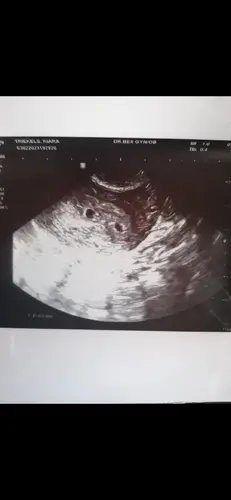

Dankjullie wel dames voor jullie reactie. Werd me gisteren gezegd dat deze grootte wat aan de kleine kant is voor 6 weken. Ik ben onderbehandeling in het zkh vanwege fertiliteittraject. Toevallig belde de verloskundige mij net op, ze willen dat ik bloed ga prikken vandaag. En ze willen opnieuw een echo doen.

Spannend. Misschien dat je gewoon net iets minder ver bent dan je dacht. Heel veel succes 馃馃徎